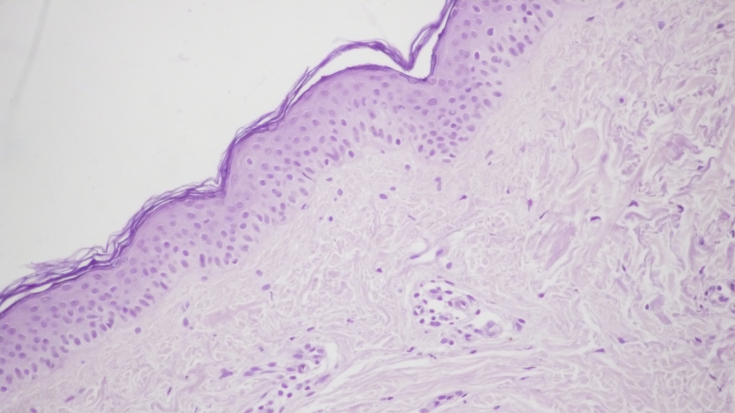

During the control histological preparation of the shkiri, before the jubilant visits, there was a signifi- cantly pronounced ignition in the dermis of the follicle crowd of lymphocytes and histiocytes. (small 1a, b). Proliferation of other vessels of the capillary and sinusoidal type was accompanied by perivascular lymphocellular infiltration (mal. 1c). In about a few hair follicles and sebaceous follicles, the ignition infiltration stimulated the proliferation of fibroblasts and the development of sclerotic processes. (small 1d).

Mal. 1. Morphological picture of the shkіri before the merry visits: flare fuse of the dermis, x200; igniter infection in the hair follicles, signs of fibrosis, x200; proliferation of other vessels of the capillary type with perivascular lymphoid-clitin infiltration, x200; sebaceous follicles with inflamed inflammation in the adjoining dermis, x200.